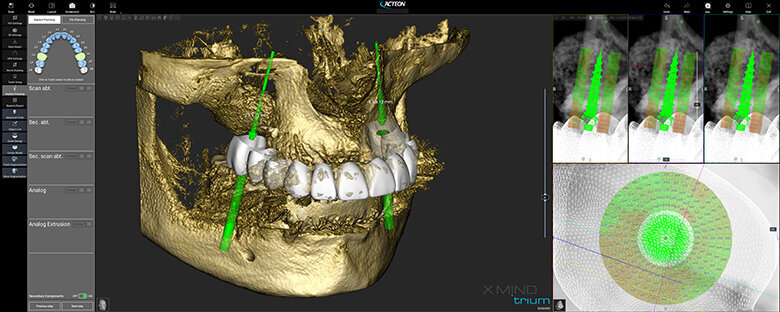

Figure 1 shows a split-mouth case with a bilateral INTRALIFT procedure: after a small crestal “booklet”-flap of approx. 7x7mm is detached, the sinus floor is safely opened with ultrasound Piezotome tips (Figs. 2 & 3), the sinus membrane then detached by the hydrodynamic cavitation effect of the Piezotome-tip TKW5 plugged into the approach canal (Figs. 4 & 5) and the subantral scaffold filled with 2cm of randomly assigned biomaterial (Figs. 6 & 7), followed by wound closure (Fig. 8). After a mean healing period of 8,4 months X-Mind trium CBCT scans were performed, the digital setup of the future bridge constructed with the AIS 3D app and the bone density determined in the sinus-lift site around a virtual implant (Fig. 9). Standardised implants (4mm in diameter and 12mm in length) were then inserted in the position of the virtual implant and insertion torque values (ITV) measured intra-surgically (test groups; Fig. 10). A total of 27 patients with sufficient native subantral crestal bone (min. crest width: 6 mm, height: 12 mm) were screened by X-Mind trium CBCT for bone density with the virtual implant (Fig. 11), the standardised implant inserted and the ITV recorded (control group). Figure 12 depicts the final result after implant insertion in the patient case shown in Figures 1–9.

As can be seen in Fig. 13, the mean CBCT bone density values in Hounsfield units (HU) at the implant site differed significantly (p <0.05) between all four test groups and the control group. The precise numerical HU values are “translated” by AIS 3D app software and are also colour-coded for easier interpretation at first glance: the brighter the green the CBCT voxel matrix shows around the virtual implant, the higher the bone density, with a virtual neutral threshold of 500 HU. Contrary, the more reddish the CBCT voxel matrix around the digital implant is depicted, the worse the biomechanical bone quality (Fig. 14). The corresponding insertion torque values (ITV) of the inserted standardised implant measured at the location of the transcrestal INTRALIFT approach (Fig. 2) also differed significantly between all test groups and the control group. Figure 15 depicts the cumulative result of the correlation between HU and ITV values for all test groups and the control group.

As the presented study proves, contemporary CBCT technology adds another outstanding feature to the general CBCT-based digital workflow as the first and only tool to safely determine the grade of primary implant stability to be expected at each individual implant site already in the planning phase before the treatment or surgery is performed (Fig. 16). By using CBCT-based bone densitometry as an integrated diagnostic step in the digital workflow, the clinician for the first time can decide individually for each patient and each implant site whether an implant insertion with immediate prosthetic loading might bear an unacceptable risk of early or delayed implant loss, and can therefore inform the patient accordingly based on evidence.